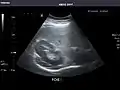

Gallbladder